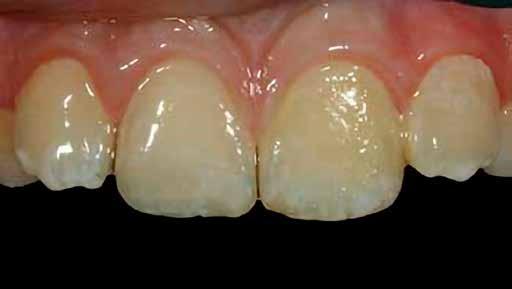

A pácienst 21 nap (14–15. ábrák) és 12 hónap (16. ábra) után ismét ellenőrizzük, hogy értékeljük az esztétikai eredményt a forma és a szín tekintetében.

13. ábra: Az UL1 emulálása polírozás közben. – 14. ábra: A helyreállítás 21 nap után.

15. ábra: A helyreállítás 21 nap után.

16. ábra: A helyreállítás 12 hónap után.